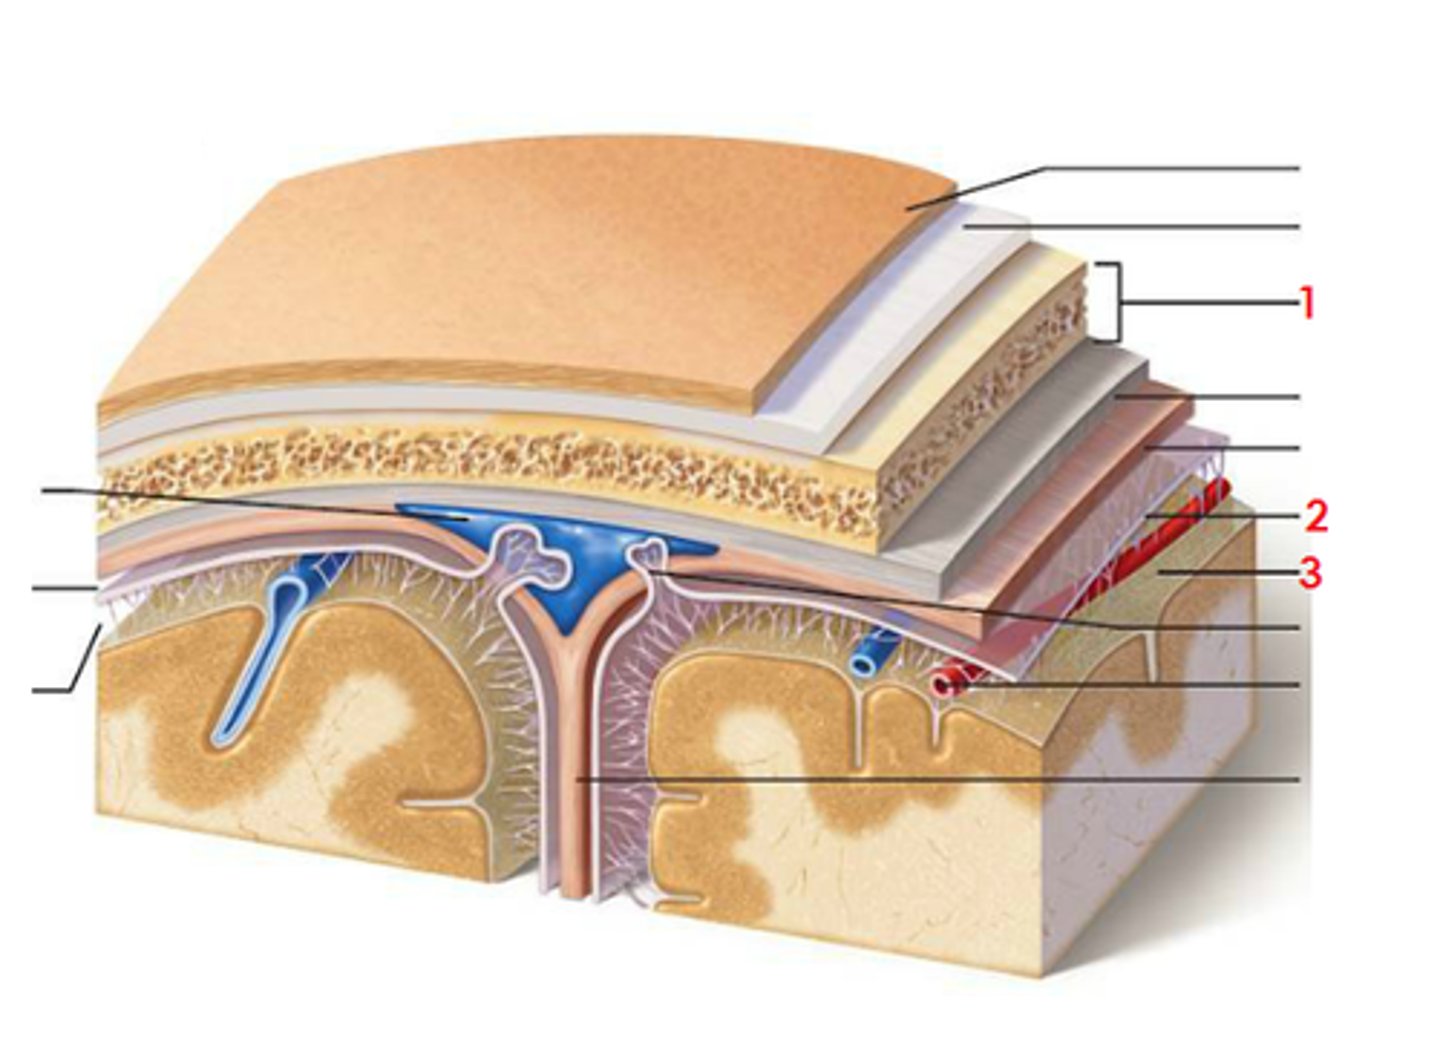

meninges

scalp, periosteium, then, 1st meningeal layer. Includes dura mater, arachnoid mater, and pia mater.

dura mater

2 layers. Periosteal layer (outer layer) and the meningeal layer - closest to next meningeal layer. This can create the dural venous sinus. right below 1 in this picture

arachnoid mater

meningeal layer on top. 2 in this picture

pia mater

sits directly on top of brain tissue. When CSF circulates, it circulates on top of brain tissue. If you try to tear pia mater away, you'll tear brain tissue. 3 in this picture